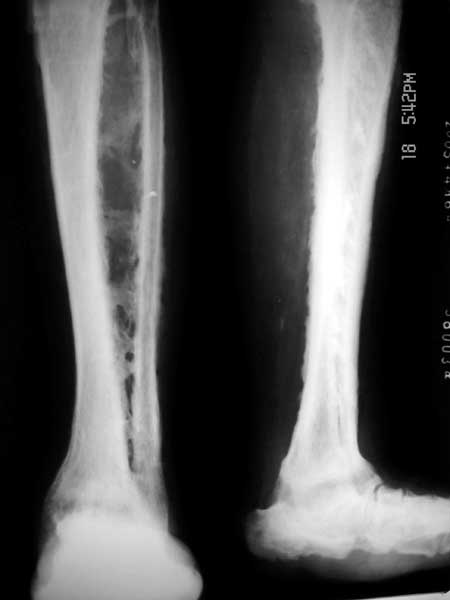

男,42岁,左踝外伤20余年。

查:体温正常,左踝部肿胀,小腿无流脓,跛行。

该病例胫腓骨之间见交叉骨质连接,其内似见杂乱骨纹,胫腓骨皮质增厚,骨髓腔模糊不清,跟骨形态边缘不整,结合外伤史考虑:左小腿(胫腓骨)骨化性肌炎.

42岁,左踝外伤20年,左踝肿胀,无流脓,跛行,胫腓骨皮质增厚,隋腔变窄增密昏暗,骨间膜骨化,跟骨

增密变形考虑1低毒感染伴骨化性肌炎2氟骨症。

左小腿软组织内有较多条片状致密影,胫腓骨相对应区骨皮质不规则,符合骨化肌炎改变.

左距骨明显碎裂变小,密度增高,跟骨密度亦增高,足弓消失,左胫骨下端有骨质吸收,踝关节间隙几近消失.考虑有1左踝创伤性关节炎;2神经营养性关节;3跟距骨缺血性坏死.

很好玩的病例。我还是考虑为低毒性感染,主要累及骨间膜。